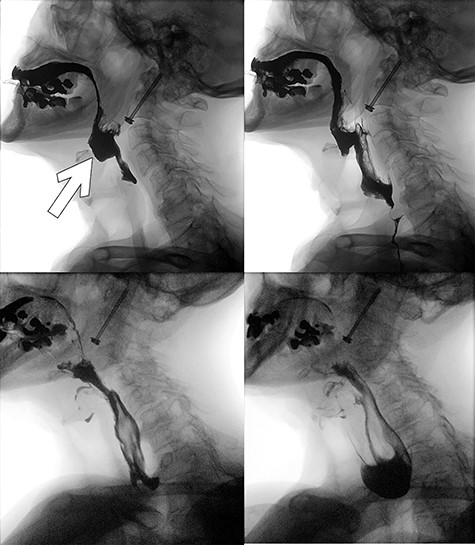

A 92-years-old man was immediately brought to the emergency department with complaints of neck pain following a fall down a flight of stairs at home. He had no comorbid illnesses and was neurologically intact. Imaging confirmed isolated type II odontoid fracture for which he had ACSF the following day. Postoperatively, he experienced dysphagia and further history revealed that he had repair of a zenker’s diverticulum ~40 years prior. A small lump was palpable in the left cervical region at the site of a previous surgical scar. Speech and language therapist, otorhinolaryngologist (ORL) and the geriatric teams were consulted while he was fed with liquid diet via a fine bore feeding tube. Preoperative cervical spine images (Fig. 1) as well as video fluoroscopy performed pre- and post-re-excision of recurrent zenker’s diverticulum (Fig. 2) are shown.

Postoperative video fluoroscopy demonstrating recurrent zenker’s diverticulum (white arrow) filling preferentially (superior left) and contrast subsequently flowing relatively easily into the esophagus following re-excision of the pouch with an incision into the cricopharyngeous muscle (inferior left and right).

His dysphagia resolved following this second operation.